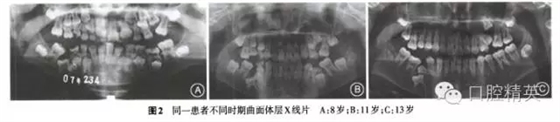

觸診下頜缺牙區(qū)未捫及膨隆,牙周健康,口腔衛(wèi)生良好。開口度及開口型無異常,雙側(cè)顳下頜關(guān)節(jié)無明顯觸痛及彈響。曲面體層x線片示,V位于5根方,遠(yuǎn)中根靠近上頜竇,V冠方已形成囊腔。5牙根近中傾斜,與4牙根重疊,牙冠位于V囊腔上方。V位于5根方,遠(yuǎn)中根接近下頜骨下緣。5牙根位于3和4牙根之間,牙冠遠(yuǎn)中傾斜,位于V冠方(圖2)。

診斷:安氏Ⅲ類亞類錯牙合畸形,5V、5V阻生。治療方案:①拔除V,V,清理V囊腔;②牽引5至正常牙列;③試牽引5,不排除牽引失敗的可能;④使用種植體支抗防止鄰牙壓低和對牙合牙伸長;⑤糾正右側(cè)后牙開牙合,若654粘連導(dǎo)致正畸治療無效,則需調(diào)整治療方案。拔除埋伏乳磨牙時(shí),錐形束CT確認(rèn)下頜神經(jīng)管位于阻生V根分叉下方(圖3),5牙根位于43舌側(cè)。手術(shù)順利拔除埋伏阻生的V、V,8個(gè)月后曲面體層x線片示牙槽骨愈合良好,可見4顆第三磨牙牙胚(圖4)。但患者家長放棄牽引治療。

乳牙阻生發(fā)生率為十萬分之一,一般發(fā)生于第二乳磨牙。乳牙阻生的原因包括牙瘤、粘連、恒牙先天缺失、牙周膜缺陷、創(chuàng)傷、牙周韌帶損傷、第一恒磨牙早萌、萌出動力不足或合并其他原因。根據(jù)本病例既往曲面體層x線片,推測患者乳磨牙阻生原因可能是恒牙胚位置異常導(dǎo)致乳磨牙萌出動力不足。拔除阻生乳磨牙的主要危險(xiǎn)是損害下牙槽神經(jīng),其次是下頜骨骨折,因此拔除前的定位非常重要,錐形束CT的應(yīng)用降低了并發(fā)癥的發(fā)生。